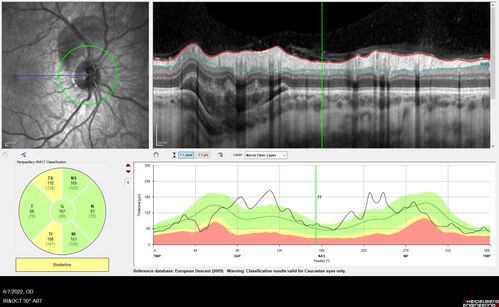

Traumatic Peripapillary Subretinal Hemorrhage

16 year old hit in eye with finger during basketball. Vision is 20/25 and there is a peripapillary hemorrhage.